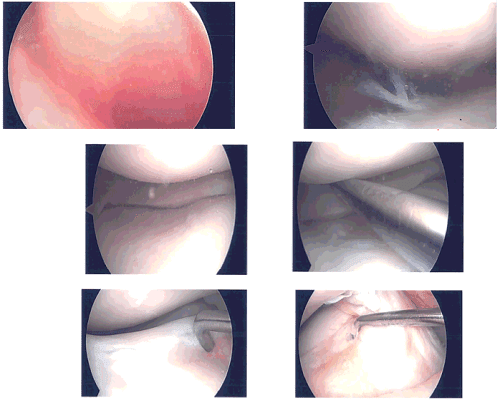

Time-out was called. A lateral entry portal was made. Arthroscopic was inserted and a medial entry portal was made for entry of the instruments. Examination showed a lateral margin fraying of the medial meniscus which was debrided with the use of shaver and Coblation wand.

There was no arthritis of the medial tibiofemoral compartment. Examination of the intercondylar region showed intact ACL. Examination of the lateral tibiofemoral compartment showed tear in the anterior horn of the lateral meniscus, which was debrided with the use of shaver and Coblation wand.

There were no arthritic changes. Examination of the patellofemoral compartment showed grade 1 to grade 2 arthritic changes in the patella, which was cleaned with the Coblation wand. Superior plica was found to be inflamed and was excised with the use of Coblation wand and shaver. Finally, pictures were taken and saved.